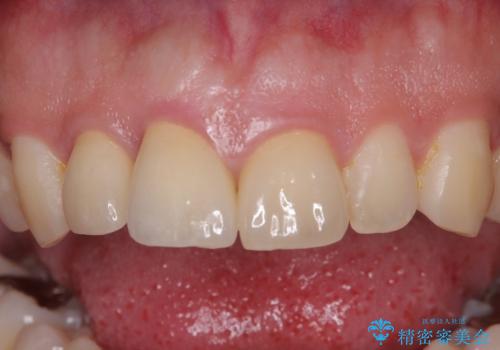

再度損傷した3本は完全に失活した状態であったため、速やかに根管治療を行い、オールセラミッククラウンにて補綴治療を行うこととしました。

- 治療費の目安: 66万円(税込)費用は治療当時の料金となります

歯が欠けるほどの強い衝撃を受けると、歯根が溶けてしまう外部吸収という現象を起こすことがあるため、補綴治療後しばらく様子を見ておりましたが、何と三度自転車事故に遭いかけてしまいました。